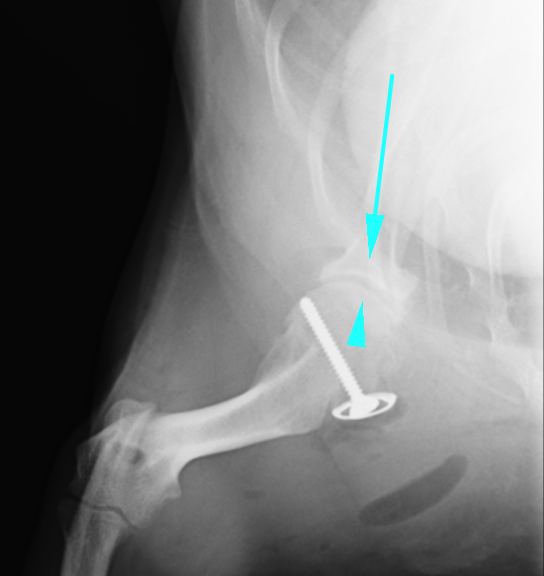

術後のX線画像です。ワッシャーとスクリューが入っているのが確認できます。また、ずれていた矢印の骨がぴったりと合い、関節がはまっているのがわかります。

横から見たレントゲンです。右が術前、左が術後です。こちらも線を引くと

右のレントゲンではオレンジと赤のラインが全く合っていなかったのが、左の術後ではピッタリとあっているのがわかると思います。